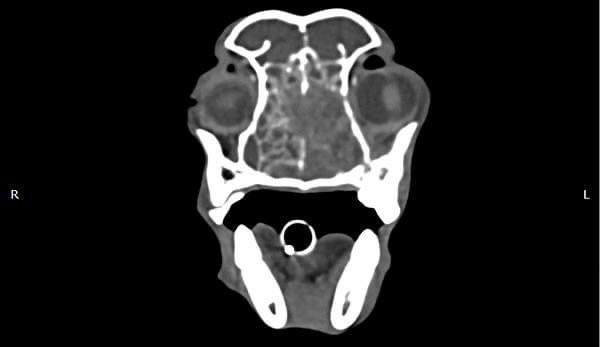

狗狗 鼻腔腫瘤 惡性上皮癌

鼻腔腫瘤的診斷需要仰賴電腦斷層掃瞄定位病灶處,同時使用鼻腔內視鏡探查、採樣才能確診,同時有這兩項設備的醫院並不多,所以臨床上並不是那麼容易確診。狗狗的慢性鼻炎維持3-4個月,越來越嚴重,他院轉診至築心,經由內視鏡+電腦斷層確認為鼻腔上皮癌,而且由於病程時間長,已經轉移至胸腔,代表壽命不長了,至少家人心中有個答案,有心理準備陪狗狗最後一段路。

狗狗 鼻腔腫瘤 淋巴癌

鼻腔腫瘤的診斷需要仰賴電腦斷層掃瞄定位病灶處,同時使用鼻腔內視鏡探查、採樣才能確診,同時有這兩項設備的醫院並不多,所以臨床事並不是那麼容易確診。狗狗如果有打噴嚏、鼻分泌物 鼻塞,對藥物治療反應不好, 就還是要做進一步檢查才會比較安心唷!

鼻上皮細胞癌

鼻腔症狀是門診中狗貓最常見的主訴之一,但在診斷上卻不那麼容易,在缺乏如電腦斷層、內視鏡、牙科X光等特定設備的情況下,門診醫師多只能嘗試性的給藥觀察,對於慢性、頑固、難治的鼻腔問題往往便束手無策了。

柴犬皮皮因長期有鼻塞、流鼻血、流鼻水的症狀來築心就診,在這之前已經換過兩間醫院,但治療效果都不太好。在一系列的評估後,我們為皮皮安排了電腦斷層以及鼻腔內視鏡的檢查,檢查後發現在皮皮的鼻腔內有疑似腫瘤的團塊,並且向後侵入鼻竇,甚至已經接近大腦。我們運用內視鏡設備採樣取得了團塊的切片,並得到鼻上皮細胞癌的診斷。